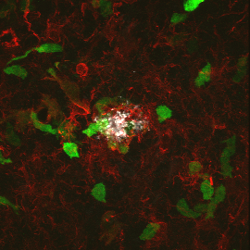

Interleukin-1-rich immune cells infiltrating the

beta-amyloid plaques seen in Alzheimer's disease;

photograph from Shaftel SS, Kyrkanides S, and

Olschowka JA, et al

from the University of Rochester; 2007